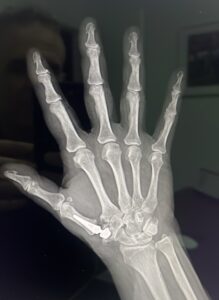

–Artroplastia total: Consiste en colocar una prótesis trapeciometacarpiana. El aspecto es similar a las que tienen las de cadera: hay un vástago que se coloca dentro del primer dedo, una cabeza esférica que articula sobre una cúpula llamada acetábulo que se coloca en el trapecio. La movilidad es completa y la fuerza también. Es la intervención que se ha realizado Nadal. De esta forma, ni pierde movilidad ni prácticamente fuerza, sobre todo de agarre. Esa articulación se ha desgastado debido al agarre de la raqueta y los golpeos todos estos años.

–Artrodesis de la base del pulgar: se usa en personas cuyos trabajos son de mucha fuerza. Consiste en dejar “sin juego” la articulación que une la base del dedo gordo con la muñeca, mediante una placa con tornillos. Si la articulación no se mueve, no duele. El trabajo de esa articulación que no funciona lo realizan otras pequeñas articulaciones de la muñeca, que deben estar sanas para poder realizar esa técnica.